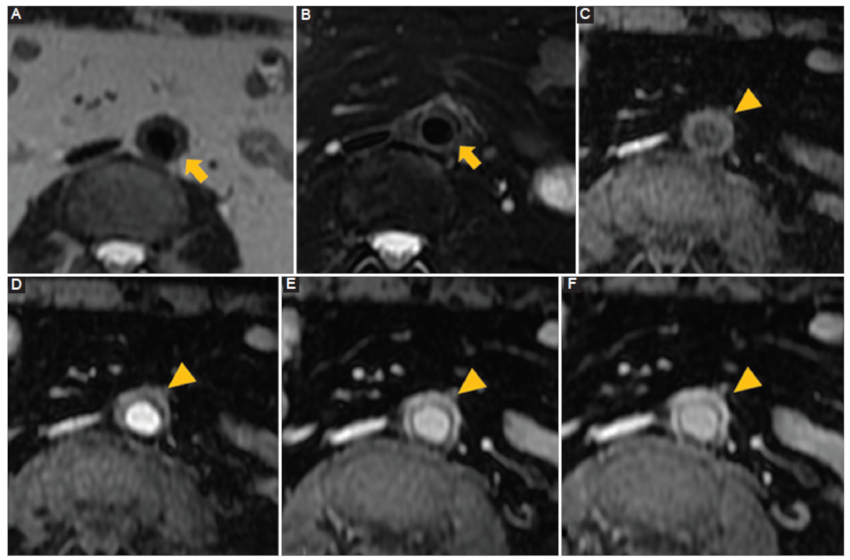

Fibrosis retroperitoneal

Proliferación de tejido fibro-inflamatorio que rodea la aorta abdominal y arterias ilíacas y con extensión hacia el retroperitoneo comprometiendo estructuras vecinas (vena cava inferior, uréteres, etc.) generalmente de origen idiopático, estableciéndose también la asociación al uso de fármacos, algunas neoplasias, infecciones, enfermedad por IgG4 y cirugías previas13. Destaca la presencia de un tejido periaórtico irregular con densidad de partes blandas que no compromete la pared posterior de la aorta (Fig. 8), que presenta realce con el contraste intravenoso y que en RM presenta señal baja ponderada en T1 con intensidad variable en imágenes ponderadas T2, que refleja el grado de inflamación activa14. En etapa aguda podemos observar compromiso del tejido graso regional y realce más ávido del contraste que en etapas crónicas (Fig. 9).

Fibrosis retroperitoneal. Hombre de 69 años. Sospecha de diverticulitis aguda. Resonancia magnética con contraste A: secuencia ponderada en T2 corte axial. B: secuencia ponderada en T2 con saturación grasa corte axial. El tejido periaórtico es hipointenso en las secuencias ponderadas en T2 y T2 con saturación grasa (flecha). C: secuencia ponderada en T1 precontraste con saturación grasa corte axial. D: secuencia ponderada en T1 fase arterial con saturación grasa corte axial. E: secuencia ponderada en T1 fase porto-venosa con saturación grasa corte axial. F: secuencia ponderada en T1 fase tardía con saturación grasa corte axial. Después de la inyección de contraste intravenoso paramagnético (gadolinio) se observa un realce progresivo del tejido de partes blandas periaórtico (punta de flecha).

Figura 9